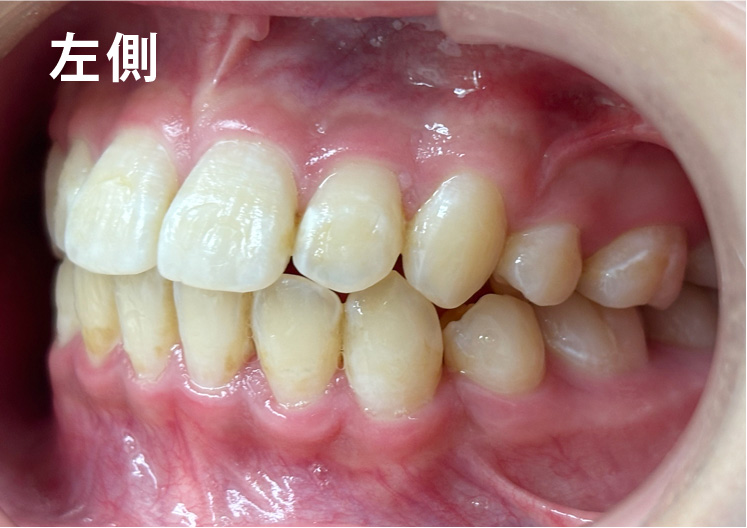

矯正bofore

矯正種類 ワイヤー矯正

症例 上下額叢生

治療期間 2021年12月〜2024年10月

性別/年代 男 13歳

治療費 748,000円

コメント

適切な時期に治療が開始できたので、歯並びだけでなく顎や顔貌も理想的に成長しました。歯磨きもしっかりできるようになりました。